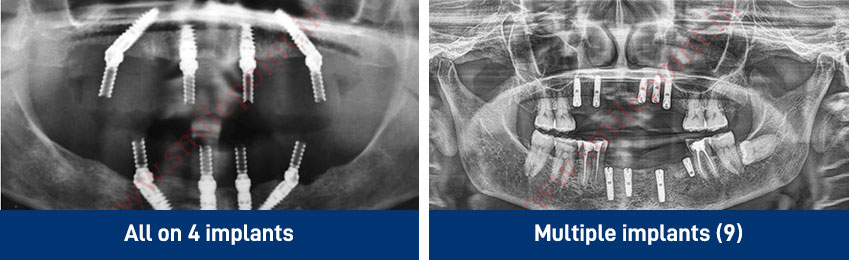

Implants